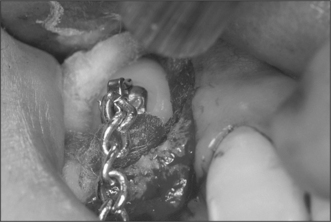

Attempts should be made to retain the keratinized tissues by employing displacement of the attached gingiva with apically or, occasionally, laterally repositioned flaps. The apically repositioned flap retains the mucogingival collar around the tooth and is displaced apically and sutured into place. The bunched gingiva will remodel as wound healing occurs (Fig. 12.1). If the tooth is misaligned, a bracket and gold chain may be etched to the canine to direct its eruptive path appropriately (Fig. 12.2).

Fig. 12.2 A bracket and gold chain bonded to the buccal surface of an exposed canine. The chain can be attached to a fixed appliance to direct the tooth into the correct location.

If the crown tip of a maxillary canine is beyond the midline of the lateral incisor root, spontaneous eruption will not usually occur and mechanical traction will be necessary. Bonding of the bracket to the tooth following its exposure (Fig. 12.5) involves a sequence of etching, washing, drying and bonding similar to that employed in conventional adhesive dentistry. Bonding is best performed in collaboration with an orthodontist to ensure the angulation and position of the bracket is appropriate in relation to the force to be applied to the tooth. During the procedure maintenance of a meticulously dry field is essential and this is facilitated by careful suction and local infiltration of epinephrine-containing local anaesthetic.